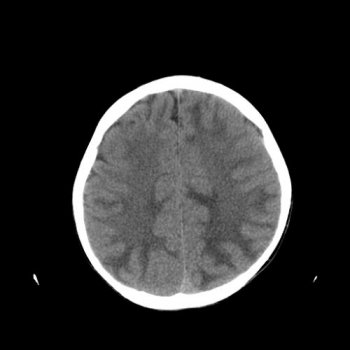

При подозрении на энцефалопатию применяются различные инструментальные методы диагностики. Рентгеновские лучи или магнитное поле помогают обнаружить объемные образования, мешающие нормальному кровообращению в сосудах головного мозга. Электроэнцефалография фиксирует электрическую активность мозга; её снижение указывает на нарушения в функциональном состоянии центральной нервной системы.